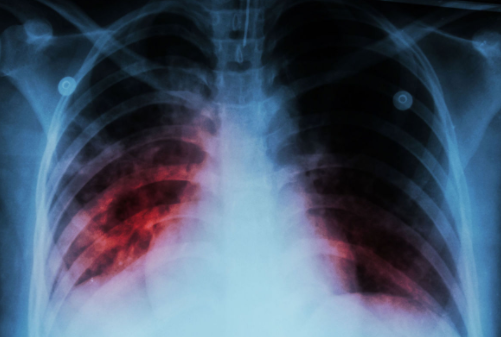

Зверніть увагу, що симптоми і те, як хвороба виглядає на рентгенівських знімках, сильно нагадує туберкульоз або центральний рак легені.

Діагностика викликає труднощі через атипового розташування запального процесу. Звичайне рентгенологічне дослідження визначає розширення середостіння, але не дає достовірної інформації про наявність вогнища запалення, тому з’являється необхідність проведення диференційної діагностики з туберкульозом і центральним раком легенів.

Одним з провідних діагностичних досліджень є рентгенографія органів грудної клітки. На знімку можна побачити розширення легеневого кореня, вогнища в зоні проекції коренів легень.

Комп’ютерна томографія дозволяє уточнити дані рентгенографії і провести диференціальний діагноз отриманого рентгенівського зображення з такими захворюваннями, як рак легень, туберкульоз, які супроводжуються подібною клінічною та рентгенологічною симптоматикою.

Справа в тому, що у випадку саме цього захворювання рентгенівські знімки можуть бути неправильно інтерпретовані.

Вогнище хвороби дає тінь і розширення кореня у легені. У цьому випадку можливі помилкові постановки діагнозу.

Щоб поставити точний діагноз прикореневій форми пневмонії, проводяться рентгенологічні обстеження. Ознаки її на знімках виражаються маленькими, світлими, округлими ділянками на легеневої тканини. Пройшовши рентген, його слід показати лікарю та отримати консультацію.